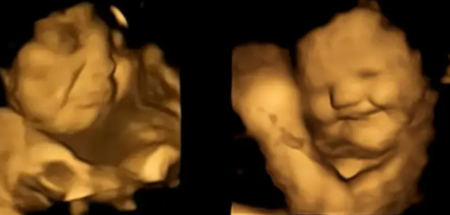

الصحة